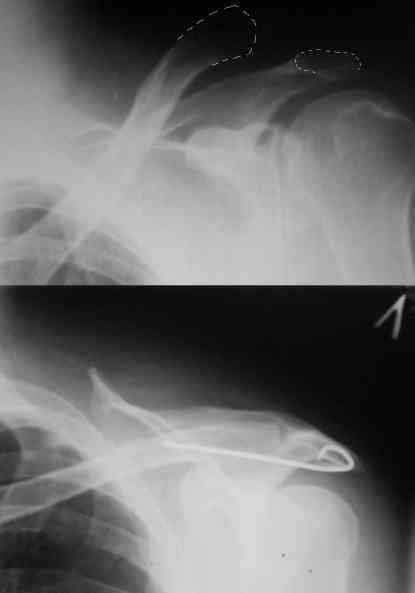

Уважаемые коллеги,высылаю протокол операции (если кому пригодится, буду рад)

Внешний вид больного (травма: 09.10.2007, операция: 11.10.2007) Ориентиры доступа: овальный – пальпируемый акромиальный конец ключицы, линейный – операционный разрез

Отпрепарированы м\ткани по передней поверхности акромиона Выведен в рану акромиальный конец ключицы

Иссечение разорванного мениска

Подготовка канала в акромиальном конце ключицы сверлом 2,8 мм

Введение крючка в подготовленный канал Дистальная часть крючка подведена под акромион и фиксирована на нем путем загибания (вывих ключицы устранен)

Изготовление крючка из стержня.

Здравствуйте.Извиняюсь за задержку. Фотографии фиксации АКС. Канал для ножки фиксатора формируется затупленным шилом, для уменьшения опасности перфорации кортикального слоя.

В некоторых клиниках активно применяли конструкции из никелида титана (с термомеханической памятью) с фиксацией за ключицу и клювовидный отросток. Сам не применял, но отзывы были хорошие а рентгенограммы красивые.